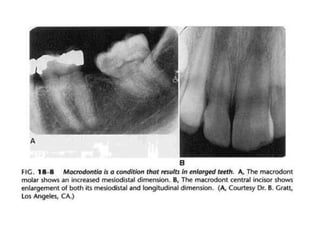

3. Macrodontia

Merupakan gigi yang ukurannya lebih besar

daripada ukuran normal.